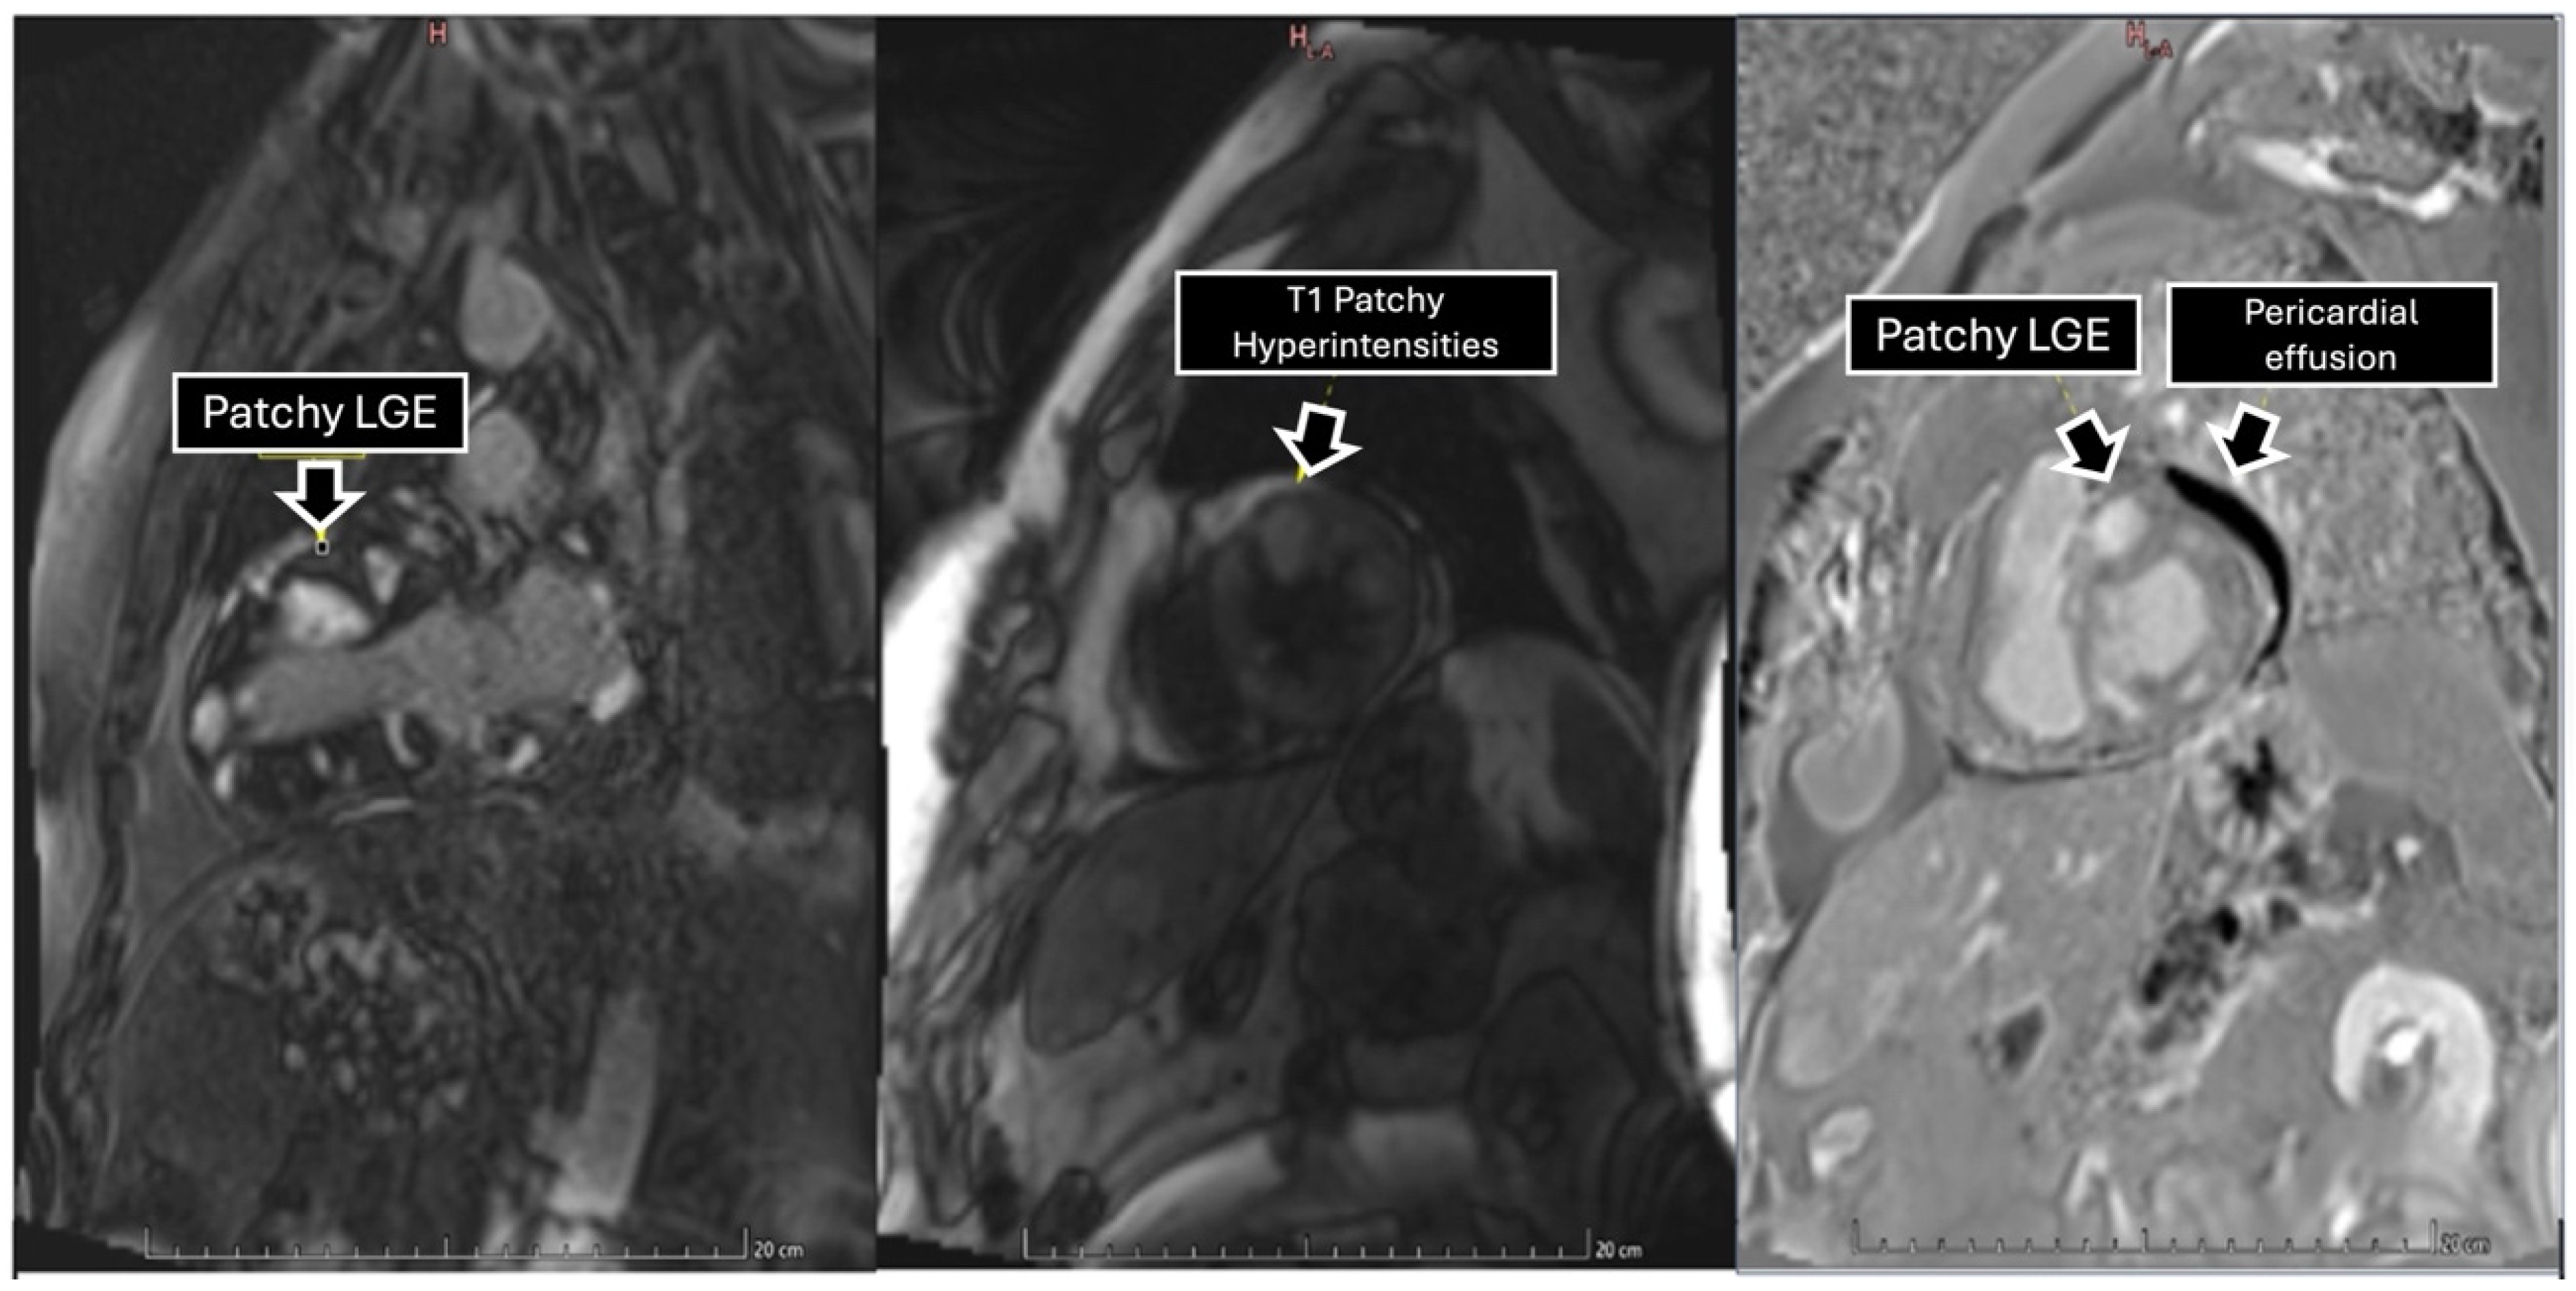

To further characterize the cardiac findings, we performed CMR, which demonstrated concentric left ventricular (LV) hypertrophy and normal global wall motion, with a preserved ejection fraction ≥70%. On T1-weighted sequences, heterogeneous cylindrical hyperintense regions with diffuse, ill-defined margins were observed throughout the LV myocardium, suggesting extensive infiltrative disease (Figure 2). Native T1 mapping revealed focal areas of low signal intensity, consistent with possible necrosis (Figure 3). Additionally, late gadolinium enhancement (LGE) demonstrated focal and diffuse predominantly mid-wall myocardial involvement, with heterogeneous gadolinium uptake in two-chamber and short-axis views, consistent with intramural necrosis and a non-coronary pattern, supporting metastatic infiltration rather than ischemic injury (Figure 4). It should be noted, however, that low native T1 values on CMR are not specific to cardiac melanoma metastases and may also be observed in other myocardial storage diseases, including myocardial iron/hemosiderin deposition and Anderson–Fabry disease [7]. Nevertheless, in the appropriate clinical context, a structured CMR-based assessment may provide incremental diagnostic value. In our patient, the CMR MASS score was 6 points, driven by infiltrative myocardial involvement, a polylobulated mass-like morphology, associated pericardial effusion, and early contrast enhancement. When low native T1 values were integrated with the patient’s oncologic history and systemic disease burden, these findings were consistent with malignant cardiac involvement.

Figure 4. Late gadolinium enhancement sequence in two-chamber and short axis views depicting tumors with heterogeneous gadolinium uptake, reflecting extensive areas of intratumoral necrosis within the myocardial wall.